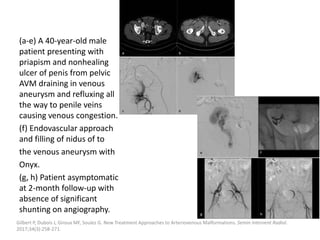

can then be treated with the sclerosant.

Müller-Wille R, Wildgruber M, Sadick M, Wohlgemuth WA. Vascular Anomalies (Part II): Interventional Therapy of Peripheral Vascular

Malformations [published online ahead of print, 2018 Feb 7]. Gefäßanomalien (Teil II): Interventionelle Therapie von peripheren

Gefäßmalformationen [published online ahead of print, 2018 Feb 7]. Rofo. 2018;10.1055/s-0044-101266.

Post-procedural care

Strict postoperative observation of the upper

airway is recommended after treatment of

patients with large cervical LMs.